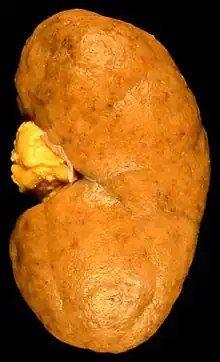

Diffuse proliferative glomerulonephritis (DPGN) is a type of glomerulonephritis that is the most serious form of renal lesions in SLE and is also the most common, occurring in 35% to 60% of patients.[1] In absence of SLE, DPGN pathology looks more like Membranoproliferative glomerulonephritis

In DPGN Most of the glomeruli show endothelial and mesangial proliferation, affecting the entire glomerulus, leading to diffuse hypercellularity of the glomeruli, producing in some cases epithelial crescents that fill Bowman's space. When extensive, immune complexes create an overall thickening of the capillary wall, resembling rigid "wire loops" on routine light microscopy. Immune complexes can be visualized by staining with fluorescent antibodies directed against immunoglobulins or complement, resulting in a granular fluorescent staining pattern. Electron microscopy reveals electron-dense subendothelial immune complexes (between endothelium and basement membrane). In due course, glomerular injury in DPGN gives rise to scarring (glomerulosclerosis). Most of SLE patients with DPGN have hematuria with moderate to severe proteinuria, hypertension, and renal insufficiency.[2]

The glomeruli are the filters in the kidneys. When working normally they will move the waste, excess electrolytes, and unnecessary fluid from the bloodstream to the urine.[8] When a person develops DPGN, over 50% of the glomeruli (diffuse) become inflamed. There is also an increase in mesangial, epithelial, and endothelial (proliferative) cells. Inflammatory cells are also rapidly developed.[9] This causes damage to the kidneys and does not allow for proper filtration.

A kidney biopsy is the most important diagnostic tool. With a biopsy, the sample will be looked at histologically. With this information, a proper diagnosis can be completed. There are many forms of glomerulonephritis, but under a microscope, DPGN will show increased cell count of polymorphonuclear cells, cellular crescents, and fibrinoid necrosis. A patient with DPGN will have more than 50% of their glomeruli involved.[4][5] If a patient has DPGN, that means they have an active form of glomerulonephritis.[10]